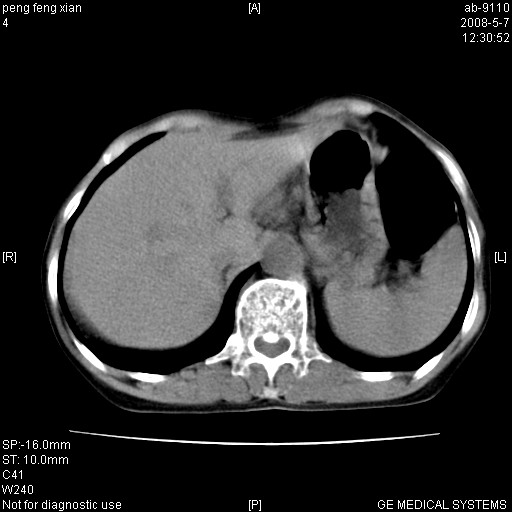

女,56岁。b超左一腹包块,考虑胃肠道肿瘤。

胃壁增厚,左前胸壁局限性隆起,考虑胃癌可能性大,建议做胃镜

典型胃癌胰体尾部受侵。

胃体部胃壁增厚,不均匀性强化,与胰腺分解欠情.

考虑:胃癌,胰腺受侵待除外.

鉴别:胃淋巴瘤(强化不明显)

建议:胃镜检查.